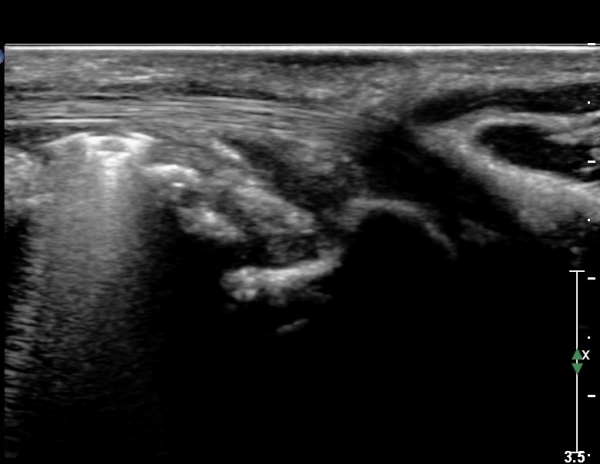

º¸ÀÌÁö ¾ÊÀ¸³ª  FPL ÈûÁÙÀÇ Àú¿¡ÄÚ ºÎÁ¾ÀÌ °üÂûµÇ°í(»çÁø 2, 3) ³»°íÁ¤¹°ÀÌ FPL °ú Á¢ÃËÇϰí ÀÖÀ½ÀÌ °üÂûµÊ(»çÁø 3)

ŽÃËÀÚ¸¦ Á¶±Ý ¸»´ÜÀ¸·Î À̵¿ÇÏ´Ï FPL Å©±â°¡ ±Þ°ÝÈ÷ °¨¼ÒÇÔ. FCR,  FDP ÁÖº¯ ¹Ì¼¼ÇÑ ¼ö¾×Àú·ù °üÂûµÊ(»çÁø4, 5)

ŽÃËÀÚ¸¦ Á¶±Ý ´õ ¸»´ÜÀ¸·Î À̵¿ÇÏ´Ï FCR¿Í FDP »çÀÌ¿¡¼­ Àú¿¡ÄÚ »óÅÂÀÇ FPL °¡ °üÂûµÇ°í °íÁ¤¹°¿¡ ÀÇÇÑ

¾Ð¹ÚÀÌ °üÂûµÊ(»çÁø 6, 7)